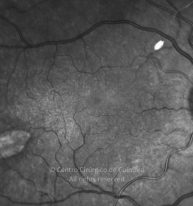

Traumatismo con un clavo en el ojo derecho hace unos 20 años, con perforación de la córnea y del iris. Catarata traumática. MAVC: 20/60 OD; OI ambliope.

Retinografía color

Cicatriz temporal. Antecedentes de vitrectomía con vítreo inferior no removido.